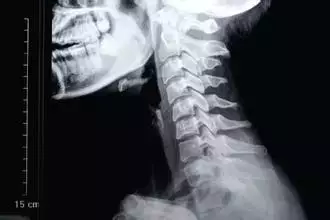

颈椎七块骨头支撑头部。只有七块骨头组成的颈椎,与肩膀构成一个沉重的十字架,支撑着分量不轻的脑袋。

如果颈椎长时间处于紧张状态,容易产生 慢性劳损、变形,一旦压迫到神经,会连带着肩部、上肢疼痛僵硬,活动受限。颈椎疾病已经成为了现代人最容易患上的疾病之一。